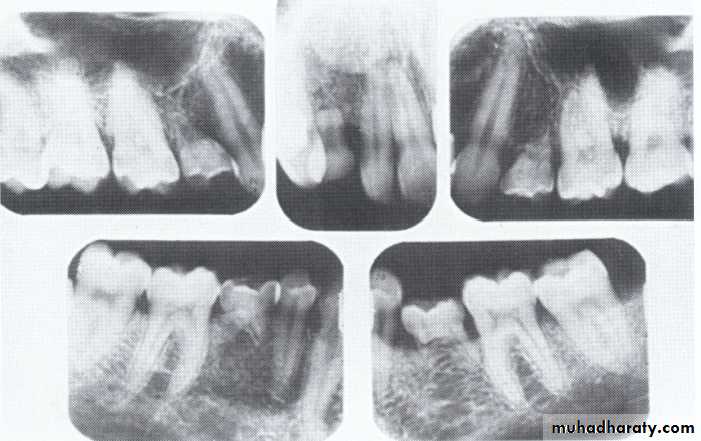

Supernumerary teeth:

Paramolar blocking the eruption of 3rd molar.

MesiodensDistomolars(4th molar)

Mesiodens

Distodens or distomolarParamolar

Supplemental